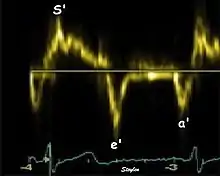

The method measures annular velocities to and from the probe during the heart cycle.

Annular velocities summarize the longitudinal contraction of the ventricle during systole, and elongation during diastole. Peak velocities are commonly used.

Diastolic function

As the ventricle relaxes, the annulus moves towards the base of the heart, signifying the volume expansion of the ventricle. The peak mitral annular velocity during early filling, e' is a measure of left ventricular diastolic function, and has been shown to be relatively independent of left ventricular filling pressure.[12][13][14] If there is impaired relaxation (Diastolic dysfunction), the e' velocity decreases. After the early relaxation, the ventricular myocardium is passive, the late velocity peak a' is a function of atrial contraction. The ratio between e' and a' is also a measure of diastolic function, in addition to the absolute values.

During the two filling phases, there is early (E) and late (A) blood flow from the atrium to the ventricle, corresponding to the annular velocity phases. The flow, is driven by the pressure difference between atrium and ventricle, this pressure difference is both a function of the pressure drop during early relaxation and the initial atrial pressure. In light diastolic dysfunction, the peak early mitral flow velocity E is reduced in proportion to the e', but if relaxation is so reduced that it causes increase in atrial pressure, E will increase again, while e', being less load dependent, remains low. Thus, the ratio E/e' is related to the atrial pressure, and can show increased filling pressure[15][16] although with several reservations.[17][18] In the right ventricle this is not an important principle, as the right atrial pressure is the same as central venous pressure which can easily be assessed from venous congestion.[19][20]